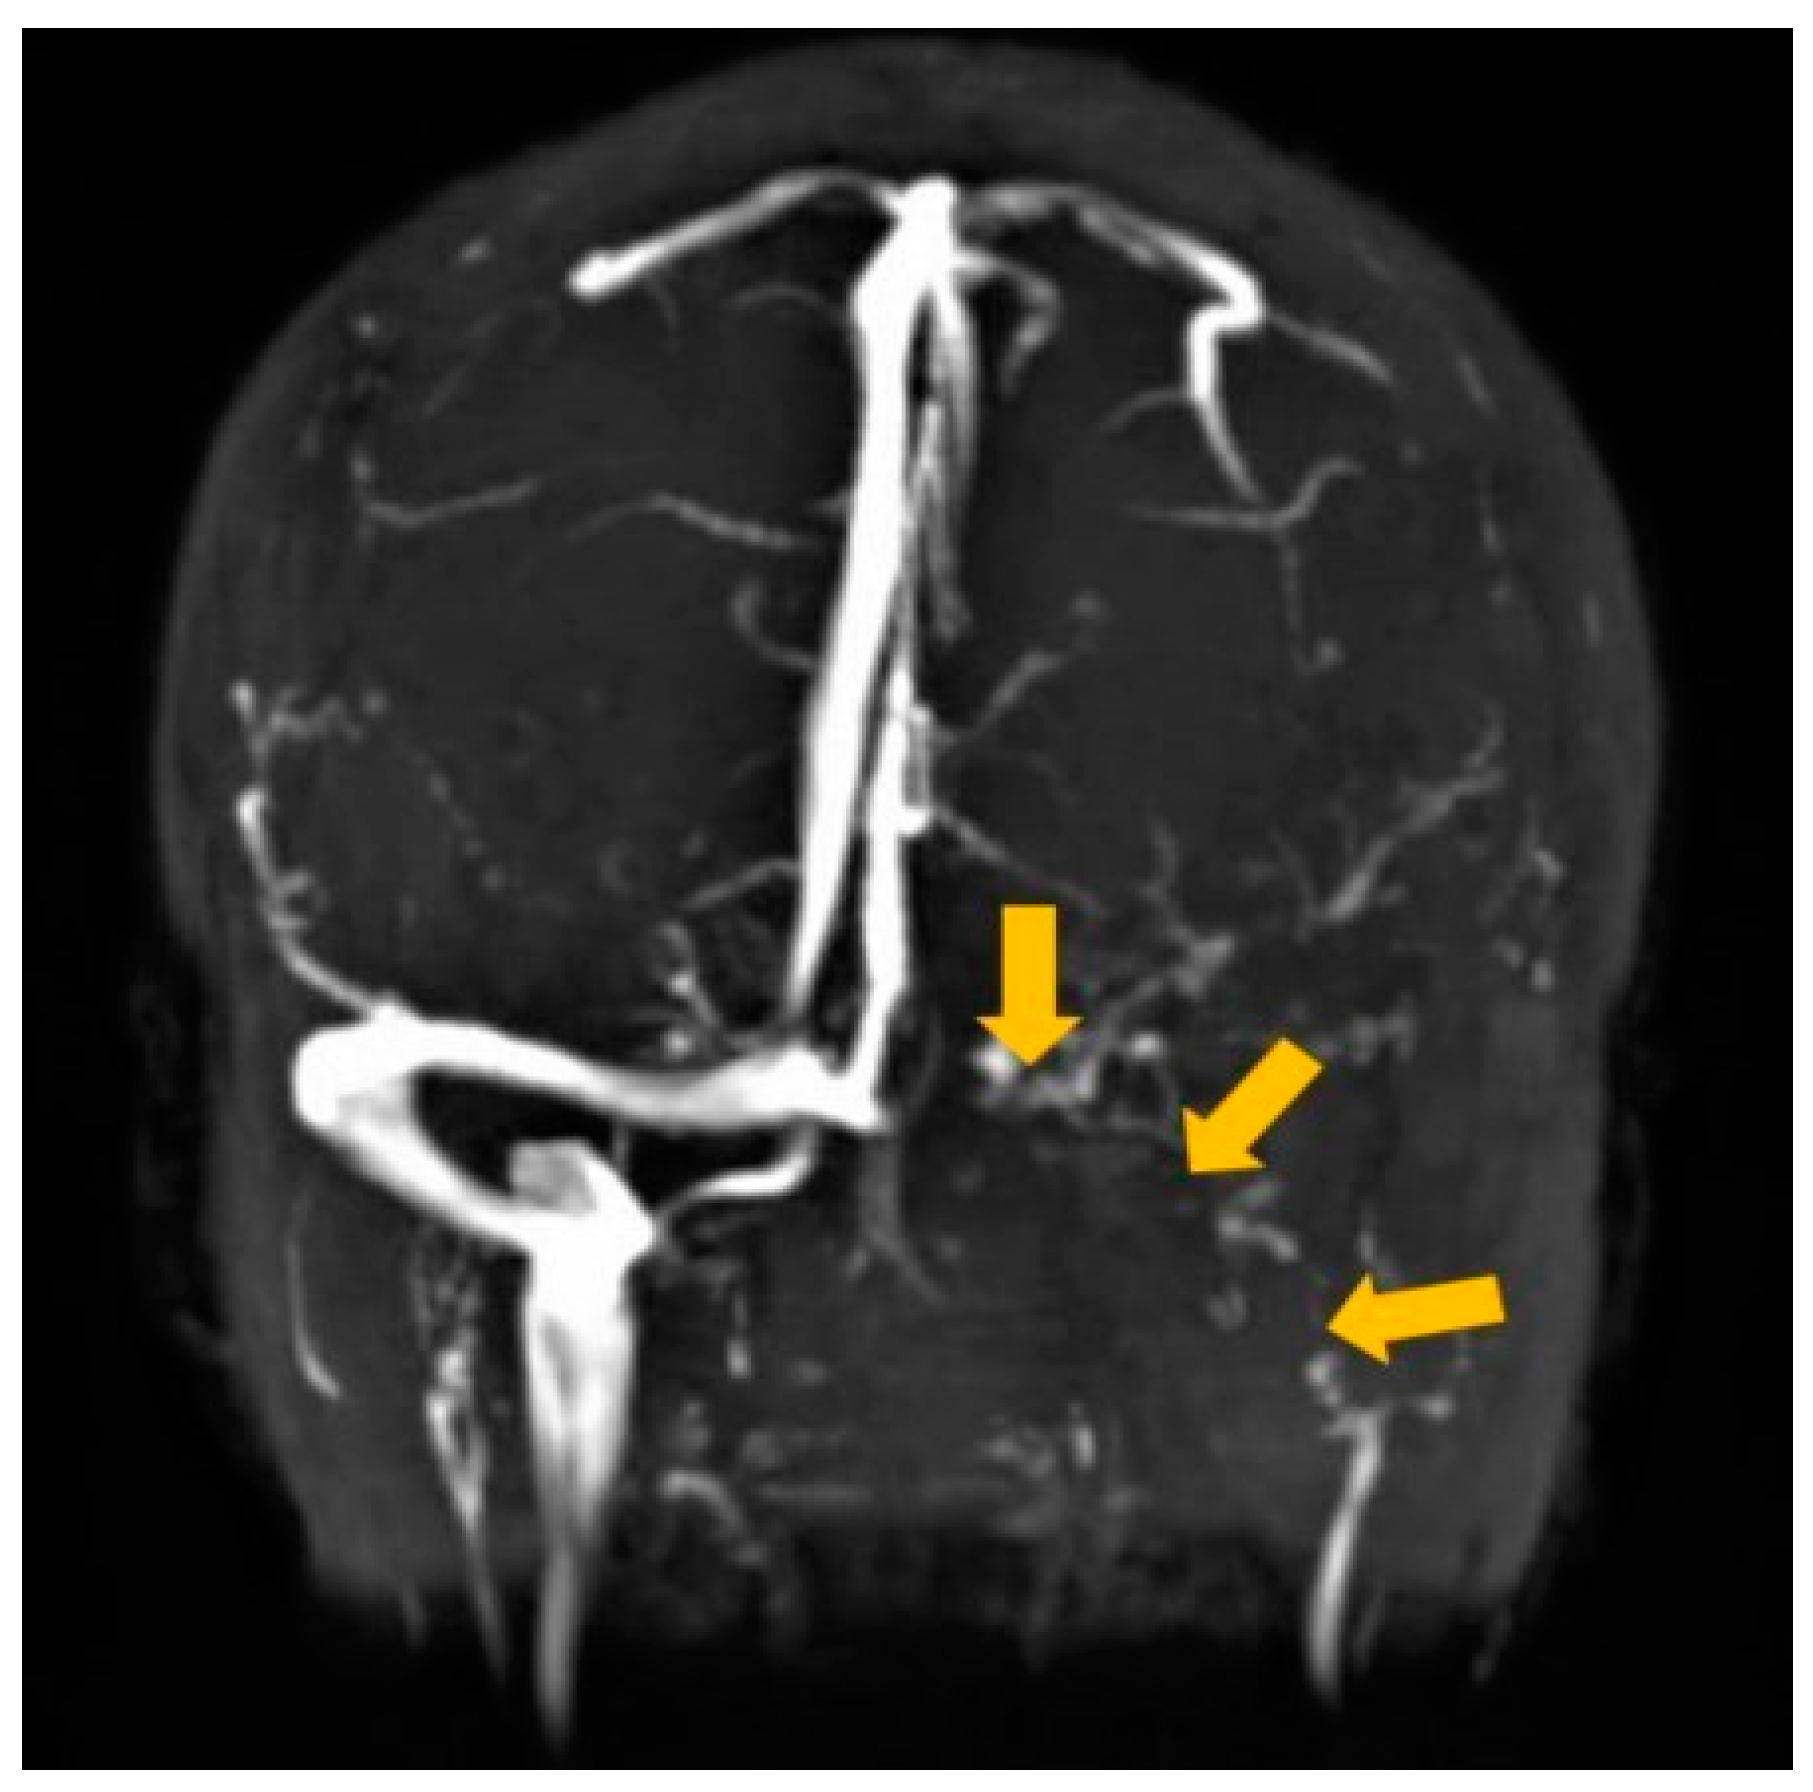

2. Case Report